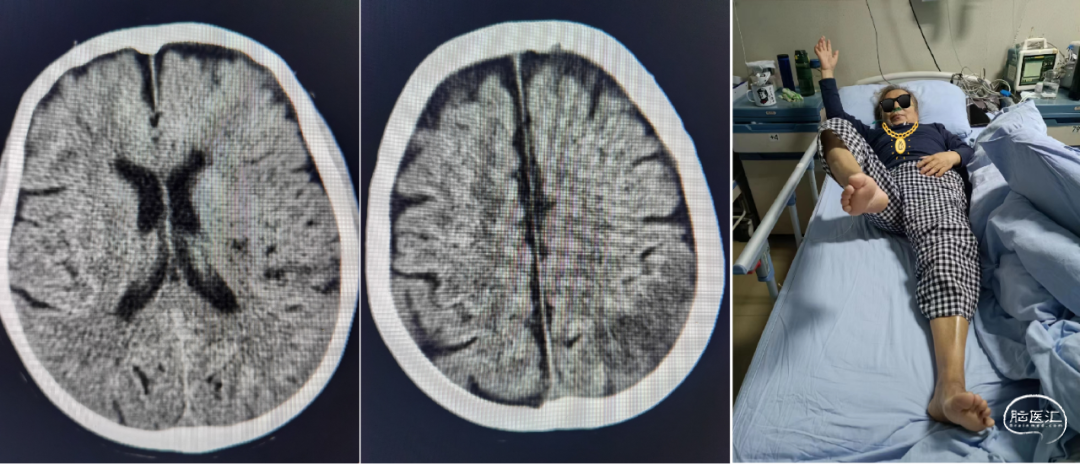

术后控制血压<140/90mmHg,第2天,患者神志清楚、言语恢复、左侧肢体肌力0级,NIHSS下降为8分,复查头部CT:左侧颞枕部局部梗死病灶;第4天,左侧肢体肌力4级,NIHSS2分。